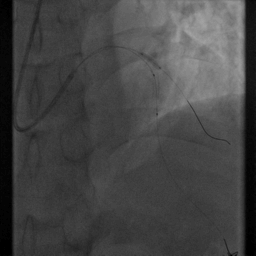

重复造影:前向血流TIMI Ⅲ级,支架贴壁良好,无夹层、残余狭窄等。

术后患者未感不适,血压120/70mmHg,心率75次/分

患者冠脉造影显示冠脉重度狭窄,活动量略大即可诱发心绞痛发作,有血运重建指征。

支架直径的选择及定位是本例手术的关键

葛均波院士采用导丝保护对角支,支架精确定位,两球囊对吻扩张的技术手段,既保证支架近端贴壁良好,又避免影响对角支开口,是手术效果良好的基础。